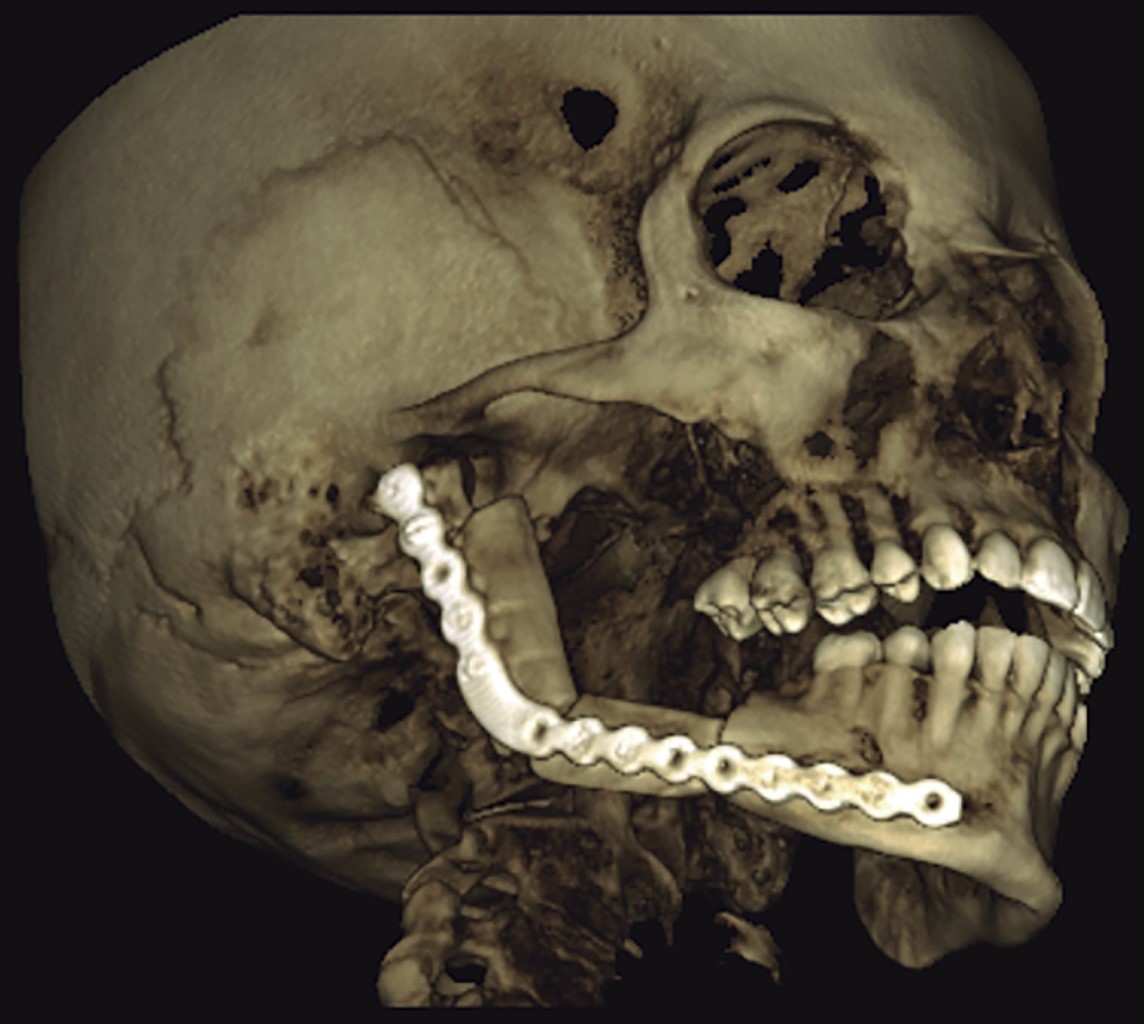

Mujer de 25 años, sin patologías crónicas ni antecedentes traumáticos previos, enviada a nuestro servicio posterior a sufrir caída de su propio plano de sustentación, con trauma dental sin pérdida de piezas dentarias que se manifestó con dolor local. Durante su protocolo de estudio se solicitó una ortopantomografía (Figura 1), observando una lesión quística en cuerpo mandibular derecho. Fue valorada por cirujano maxilofacial, quien realizó una biopsia de la lesión, con resultado de ameloblastoma uniquístico. A la exploración física se encontró asimetría facial a expensas de aumento de tamaño mandibular derecho (Figura 2), el cual no había sido percibido por la paciente. Se hizo la planeación prequirúrgica mediante tomografía de macizo facial y pierna derecha, con reconstrucción ósea, así como impresión de moldes anatómicos tridimensionales y la planeación de las osteotomías (Figura 3). El procedimiento se realizó previo marcaje convencional de pierna derecha; se tomó el peroné respetando 7 cm proximales y distales, con una isla cutánea de 2 × 5 cm. Al mismo tiempo se realizó la resección del tumor, disecando el cuerpo mandibular derecho y la rama ascendente hasta el cuello condilar ipsilateral, así como preparación de la arteria y vena facial derecha. Se procedió a la anastomosis término-terminal con prolene 9-0 con la arteria y vena facial. Posteriormente se realizaron las osteotomías según las guías de corte. Se fijó el colgajo de peroné en su zona receptora con una placa anatómica 2.0 previamente doblada. Se tomaron estudios de imagen en el postoperatorio, así como un seguimiento fotográfico en su evolución durante seis meses después de su cirugía, en la cual observamos una adecuada evolución clínica y radiológica, sin complicaciones postoperatorias y con una simetría facial satisfactoria (Figuras 4 y 5).

Figura 4